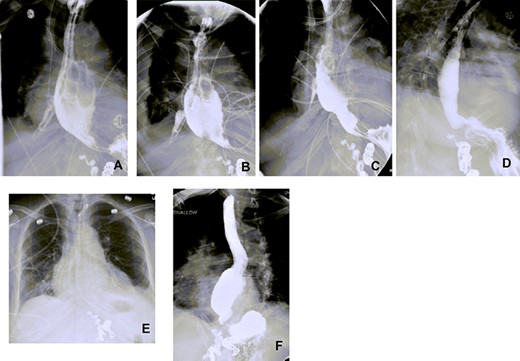

Esophagograms at various stages postadmission showing improvement in the size of the esophageal defect. (A and B) d13 and d19 Postadmission, respectively. NP tube in place ending into the right pleural space cavity. (C) d26 Postadmission with NP tube now retracted 5 cm, with decrease in the contrast extravasation seen. (D) d33 Postadmission with NP tube now removed showing no contrast extravasation seen with defect now healed. (E) CXR d41 postadmission showing improved right-sided pleural effusion and consolidation with no NP tube in place. (F) Outpatient follow-up esophagogram (d64 postadmission), (NP—nasopleural).

We found that by day 16 (d16) postdiagnosis of perforation, we were able to start pulling back on the tube. Further pulling back of the NP was dictated by improvement we saw on subsequent esophagograms. By d30, NP was removed and follow-up of esophagogram on d33 showed no extravasation of the contrast, suggesting healed perforation. She was started on sips of water and diet slowly advanced with soft regular diet 2 weeks postdischarge (Figs 2 and 3).